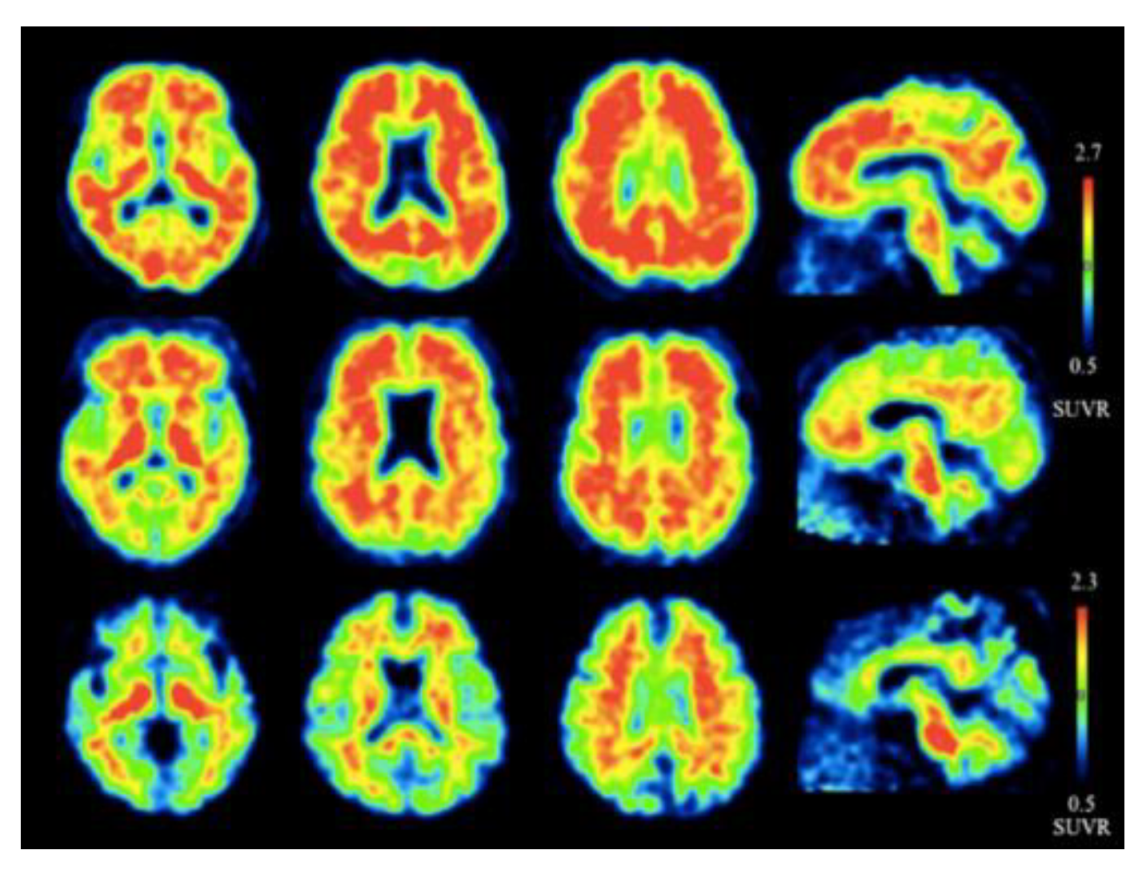

Figure 5.

Representative axial and sagittal (18F)flutemetamol images of AD (upper row), mild cognitive impairment (middle row), and healthy controls (lower row) for the detection of Aβ [57]. Extensive uptake of flutemetamol can be observed in the cortical regions of AD and mild cognitive impairment patients. Images are reprinted with permission of the publisher [57].